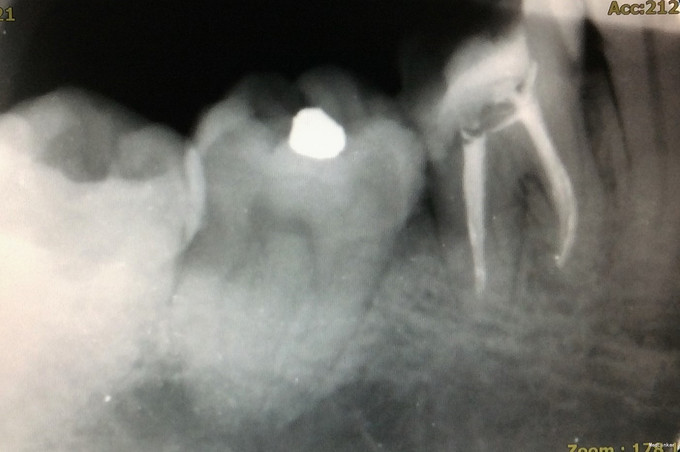

检查:46牙合面见大面积树脂充填物,部分树脂材料脱落,远中可探及继发龋,深,可探及穿髓孔,冷刺激迟钝,热刺激迟钝,电活力测试58,探(+),叩(-);牙龈及牙槽粘膜未见窦道,根尖区扪诊无不适。 X线检查:牙体组织见大面积高密度影,远中影像密度减低,累及髓腔;根尖周未见低密度影;远中牙槽嵴顶高度降低。

诊断:46牙慢性牙髓炎 治疗:46牙根管治疗+充填修复+桩冠修复 治疗经过: 首诊:去除原树脂充填物,去净龋坏,开髓,止血,封“三聚甲醛”。 首次复诊:46牙上橡皮障,揭全随室顶,显微镜下探查根管口,3根管牙,清理髓腔,#08,#10,#15不锈钢K锉疏通根管,根测仪测量根管长度,近颊根19mm,近舌根18.5mm,远中根20mm;EDTA润滑剂作用下,机用镍钛器械Protaper清扩至#2506锥度,远中根#3004,K锉疏通至#40;示尖到位;超声荡洗,次氯酸钠冲洗,干燥,根管内封氢氧化钙,髓腔置干棉球,CAVITON暂封。 二次复诊:46牙上橡皮障,去暂封,荡洗根管,次氯酸钠冲洗,干燥根管,AH糊剂加大椎度牙胶充填根尖段根管,热牙胶封闭上段根管;远中根预备纤维桩道,粘接纤维桩,行牙体树脂粘接修复。建议观察1周,若无明显不适,至修复可行冠修复。建议牙周科会诊46牙。

讨论: 1、下颌第一磨牙3根管最常见,上图清晰展示了开髓后根管口的分布。寻找根管口应注意寻找是否有远舌根,因为远舌根通常位置靠近远中边缘,若随室顶没揭全,易遗留。 2、根管预备应注意根尖孔大小。下颌磨牙通常远中根根尖孔较近中根根尖孔直径更大,行预备时应注意用K锉试探根尖孔预备是否恰当。 3、AH糊剂调拌的状态可能会影响根充的质量。本病例中,近中根、远中根均有不均匀高密度影,为相对较稠的AH糊剂。根充时应注意AH糊剂是否已固化,且应在根管中上下提拉主牙胶尖数次以使糊剂充分到达根尖处,且均匀分布于根管内。 4、若远中根根管粗大,可充填副尖以更好地封闭根尖段。 5、从该病例中可发现,远中根根尖孔开口应位于远中,不在根尖。因根尖孔的解剖位置差异大,根管治疗应充分利用根测仪测量准确的长度,不能仅凭X线片来判断。